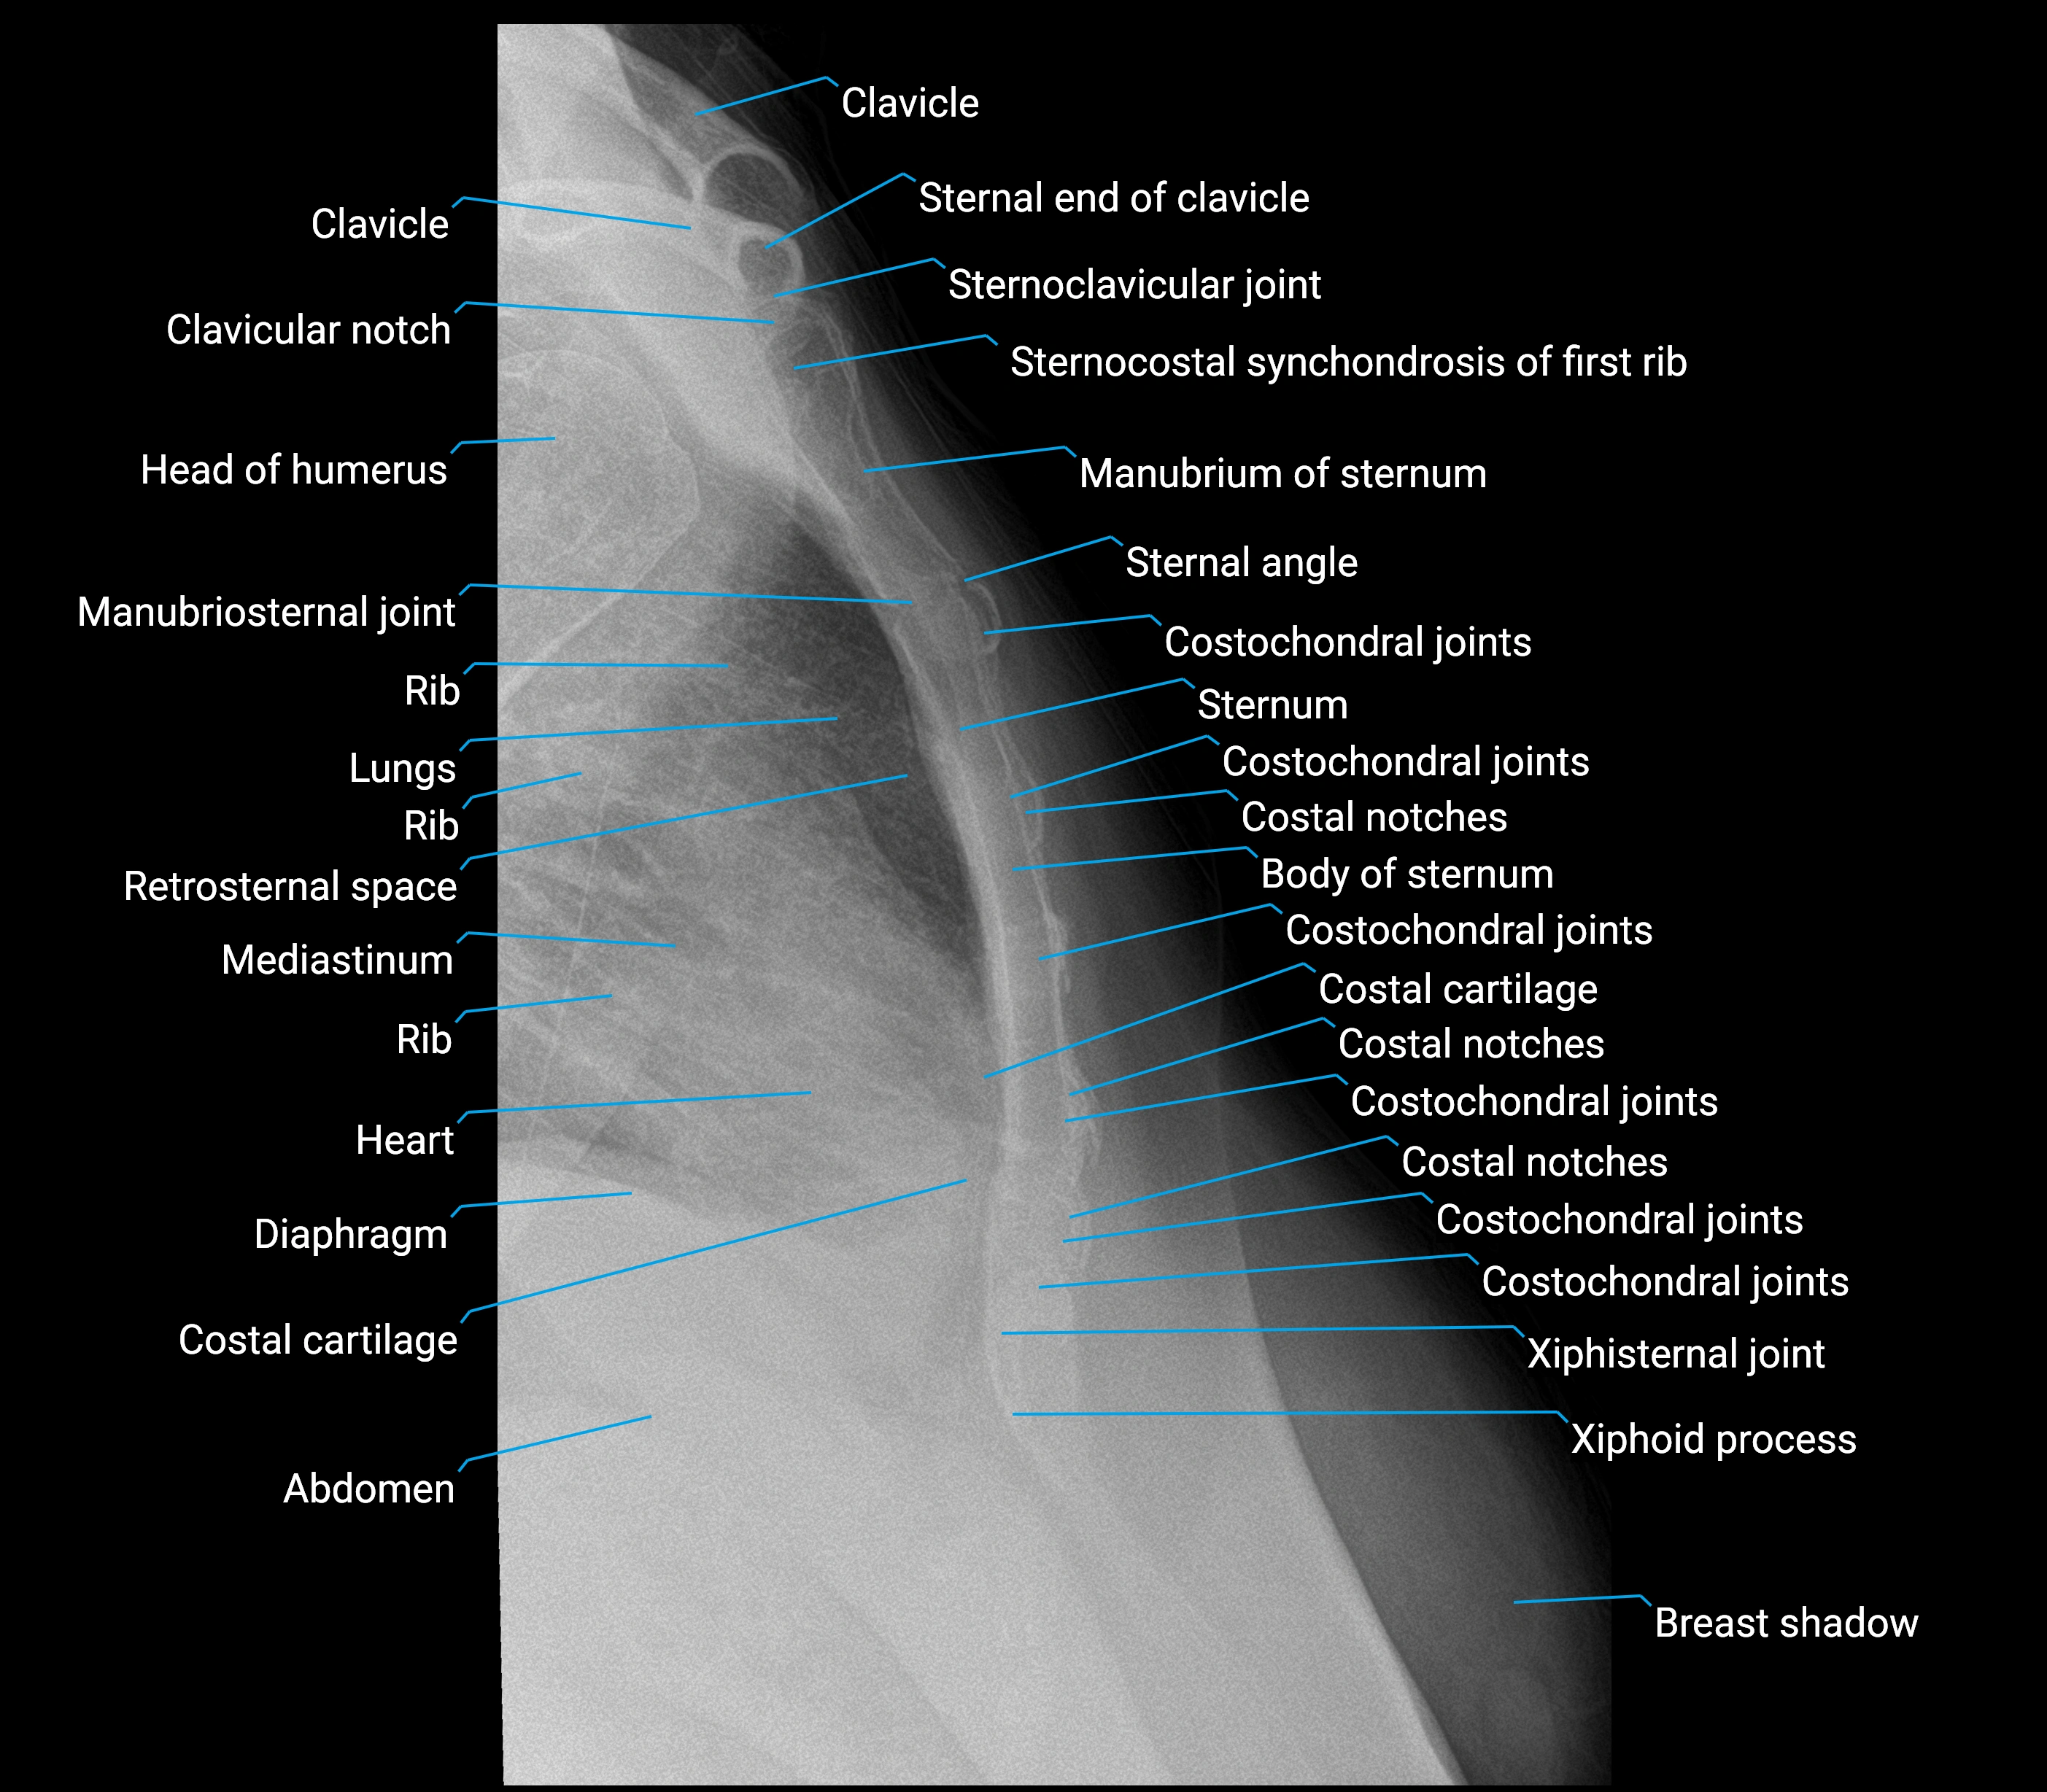

Body of sternum

The body of the sternum, also called the mesosternum, is the elongated central portion of the sternum. It lies between the manubrium superiorly and the xiphoid process inferiorly, connected by the sternal angle (angle of Louis) at the manubriosternal joint. The body is flat, elongated, and slightly convex anteriorly and concave posteriorly, contributing to the anterior wall of the thoracic cage. Laterally, it articulates with the costal cartilages of the second through seventh ribs, forming a major structural component for rib attachment. It provides protection for the heart, great vessels, and anterior mediastinal structures, as well as an anchoring surface for multiple thoracic and abdominal muscles.